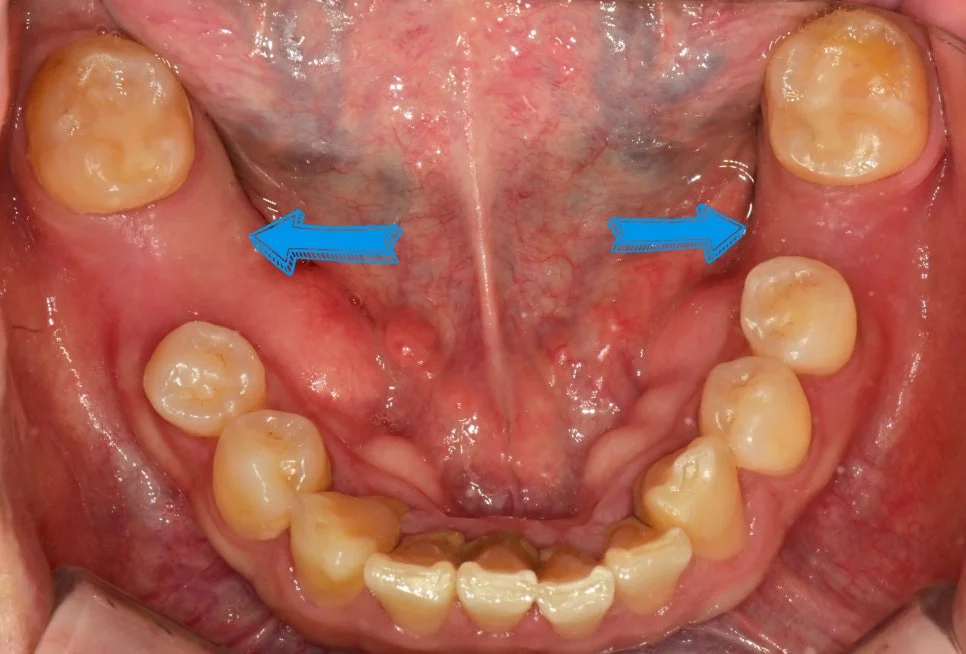

미국에 거주하는 분이 한국에서 임플란트 하는 법, feat 임플란트 하나 더 심은 이유

미국에 거주하는 환자분의 한국 임플란트 치료 사례입니다. 추가 비용 없이 fixture를 하나 더 식립해, 유착 실패나 향후 보철 문제에 대비할 선택지를 남긴 과정을 설명합니다.